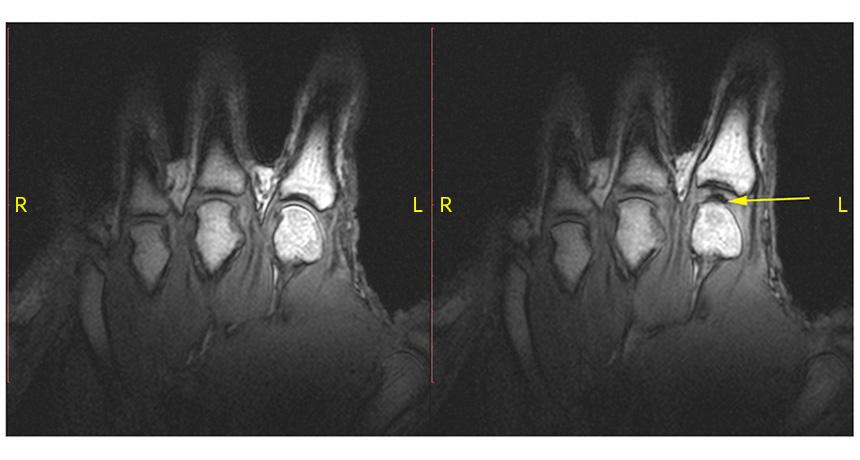

A knuckle at rest (left) pops when pulled. The sound comes from a bubble (right, yellow arrow) opening up in the joint.

G.N. Kawchuk et al/PLOS ONE 2015 (CC BY 4.0)

As a finger is pulled, tension mounts in the knuckle joint. Fluid rapidly accumulates there. This shows up as a white spot on the MRI picture. Suddenly, a cavity — or bubble — opens. As it does, the knuckle makes a pop. It’s much like the sound that a suction cup makes as someone pulls it off of a glass window, Kawchuk says. The joint’s bubble can last for up to 20 minutes. And until it goes away, the knuckle will not be able to crack again.